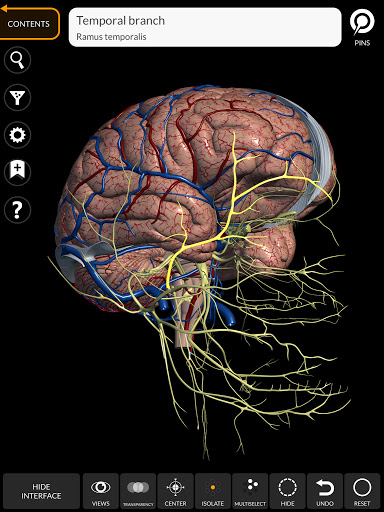

"Anatomía - Atlas 3D" permite estudiar la anatomía humana de forma fácil e interactiva.

A través de una interfaz sencilla e intuitiva es posible observar cada estructura anatómica desde cualquier ángulo.

Los modelos anatómicos 3D son especialmente detallados y con texturas de hasta una resolución de 4k.

La subdivisión por regiones y las vistas predefinidas facilitan la observación y el estudio de partes individuales o grupos de sistemas y las relaciones entre los diferentes órganos.

MODELOS ANATÓMICOS 3D

nervioso • Sistema respiratorio • Sistema digestivo • Sistema urogenital (masculino y femenino) • Sistema endocrino • Sistema linfático • Sistema ocular y auditivo CARACTERÍSTICAS • Interfaz sencilla e intuitiva • Rotar y hacer zoom en cada modelo en el espacio 3D • Opción para ocultar o aislar uno o varios modelos seleccionados • Filtro para ocultar o mostrar cada sistema • Función de búsqueda para encontrar fácilmente cada parte anatómica • Función de marcador para guardar vistas personalizadas • Rotación inteligente que mueve el centro de rotación automáticamente • Función de transparencia • Visualización de músculos a través de niveles de capas desde las superficiales hasta las más profundas • Al seleccionar un modelo o un pin, aparece el término anatómico relacionado • Descripción de los músculos: origen, inserción, inervación y acción • Mostrar/ocultar interfaz de usuario (muy útil con pantallas pequeñas) MULTILINGÜE • Los términos anatómicos y la interfaz de usuario están disponibles en 11 idiomas: latín, inglés, francés, alemán, italiano, portugués, turco, ruso, español, Chino, japonés y coreano • Los términos anatómicos se pueden mostrar en dos idiomas simultáneamente REQUISITOS DEL SISTEMA • Android 8.0 o posterior, dispositivos con al menos 3 GB de RAM Reversi